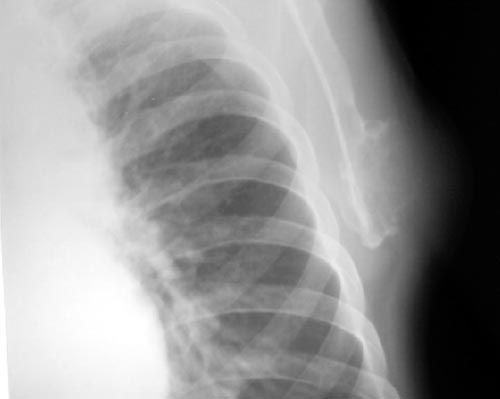

以下是引用lkc8963在2006-3-20 0:01:00的发言:[br]骨软骨瘤基本可定,至于有没有恶性变,本例依据不足,似见软块但皮下脂肪尚清,不知临床表现倒底有没有肿块还是突起?建议ct或穿刺检查。